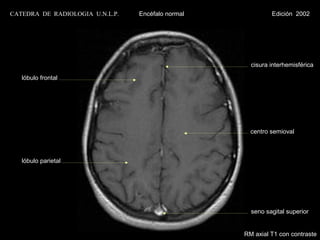

CATEDRA DE RADIOLOGIA U.N.L.P.   Encéfalo normal            Edición 2002

cisura interhemisférica

lóbulo frontal

centro semioval

lóbulo parietal

seno sagital superior

RM axial T1 con contraste